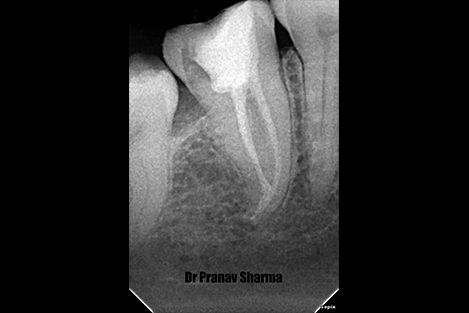

Xray